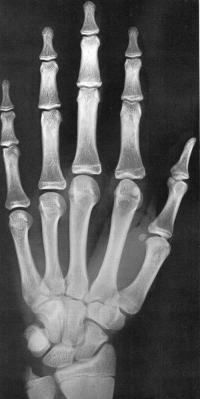

Sexo Masculino

Recém-Nascido

idade óssea - RN